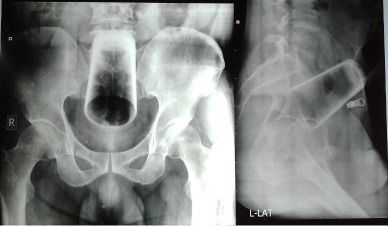

x-ray yang menunjukkan gelas tersangkut dalam dubur. Foto: Journal of Nepal Medical Association |

Seorang pria di Kathmandu, Nepal nekat memasukkan gelas berukuran 12 cm ke dalam anus demi kepuasan pribadinya ketika mabuk. Mulanya, pria yang tak disebutkan namanya ini beralasan bahwa dia memasukkan gelas tersebut ke dalam anusnya secara tidak sengaja.

Pria tersebut akhirnya mencari bantuan setelah gagal mengeluarkan gelas tersebut dari tubuhnya secara mandiri. Kasus ini dicatat dalam Journal of Nepal Medical Association.

Dalam jurnal itu disebutkan pria ini tidak bisa buang air besar (BAB) selama dua hari. Tetapi, pria ini masih bisa buang angin.

Sementara pria tersebut dilaporkan mengalami kesakitan, perutnya tidak mengalami bengkak dan anusnya tidak mengalami cedera atau perdarahan. Hasil x-ray pria tersebut menunjukkan gelas air dalam posisi terbalik di rektum atas dan usus besar.

Tim dokter sempat mengalami kesulitan ketika ingin mengeluarkan gelas dari tubuh pria tersebut. Sebab, gelas tersebut berbahan dasar kaca dan berisiko pecah apabila ada kesalahan prosedur.

"Karena kacanya tinggi, terbalik dan terjepit rapat," ujar tim medis dikutip dari Daily Mail, Senin (27/3/2023).

Tak ada pilihan lain, dokter terpaksa memotong perut pria tersebut dan melakukan enterotomi sigmoid atau membuat sayatan di dalam usus. Cara tersebut akhirnya berhasil mengeluarkan gelas dalam perut pria tersebut.

Seminggu setelah operasi, pria tersebut diperbolehkan pulang dari rumah sakit. Janji tindak lanjut yang dilakukan dua bulan setelahnya, mengungkapkan tidak ada komplikasi.